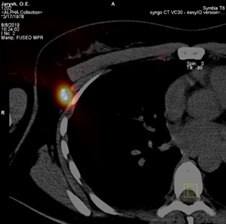

Медичні закупівлі України вперше уклали трирічний договір із виробником Merck Sharp & Dohme (США) на закупівлю інноваційного препарату пембролізумаб (торгова назва – Кітруда) для лікування пацієнтів з нерезектабельною або метастатичною меланомою — одного з найагресивніших онкологічних захворювань

Пембролізумаб — один із ключових препаратів сучасної онкоімунології, який посилює здатність імунної системи виявляти та знищувати злоякісні клітини.

Препарат показує хороші результати при пізніх стадіях меланоми, коли хірургічне втручання вже неможливе, а імунотерапія стає єдиною ефективною стратегією боротьби з хворобою. Це не просто препарат — це надія, підкріплена наукою та практикою.